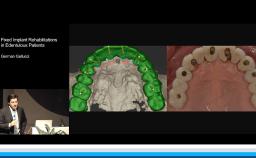

This lecture describes the treatment approach using a digital workflow for fixed implant rehabilitation of edentulous jaws. Treatment sequence, implant number and distribution, and the implant-prosthetic design are all thoroughly discussed. The speaker presents a detailed approach to full-arch rehabilitation using the digital workflow, which includes immediate loading with fixed screw-retained provisional prostheses during the healing phase. Other techniques presented include use of transitional implants and segmentation of full-arch prostheses. Evidence is presented on digital versus conventional implant impressions and the anterior-posterior distribution of implants in relation to survival.